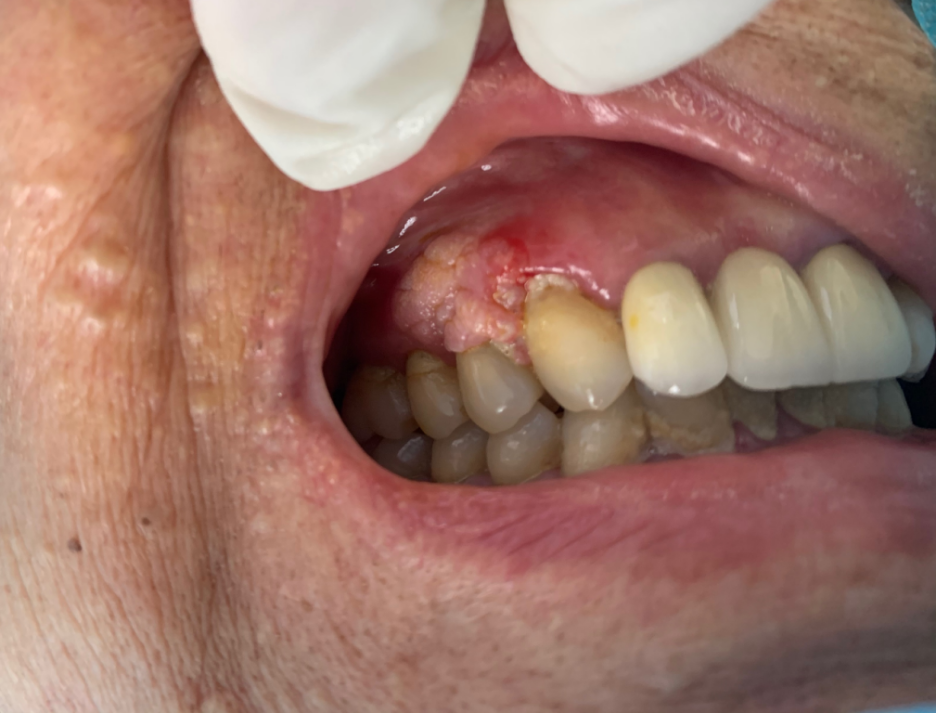

虽然,口腔尖锐湿疣癌症在发生早期,病症表现是比较显著的。之所以许多人不能发觉男性尖锐早期症状图片,这与其不了解该病症的病症是密切相关的。口腔尖锐湿疣癌症发生部位主要集中在舌绑带及其附近。发病早期,其局部瘙痒凸起呈乳房状、菜花状、鸡冠状,早期病状较小,有黄豆大,然后渐渐成长到豌豆大小,其边界与周围皮肤比较清晰,麻疹数量会在1-10个之间不等。其病状颜色多数淡黄色,部份是鲜绿色,稍稍触及,就容易流血。在显微镜下观察口腔尖锐湿疣病症,可发觉重病部位的表皮呈弥漫性角化不全,同时伴随存在有乳房瘤样囊肿的情况。另外,发病部位还可见空泡细胞。

口腔尖锐湿疣病人自觉有疼痛或痒感。发病部位比较典型的外形病症是其表面粗糙、呈现有菜花状、鸡冠状等,通常,仔细利用肉眼观察就可看出。对于不具有典型病症的疣体,可利用甲酸白试验进行鉴定,或去诊所做组织病理检测,若是可发觉有凹空细胞,即可明晰确诊患有湿疣疾患。